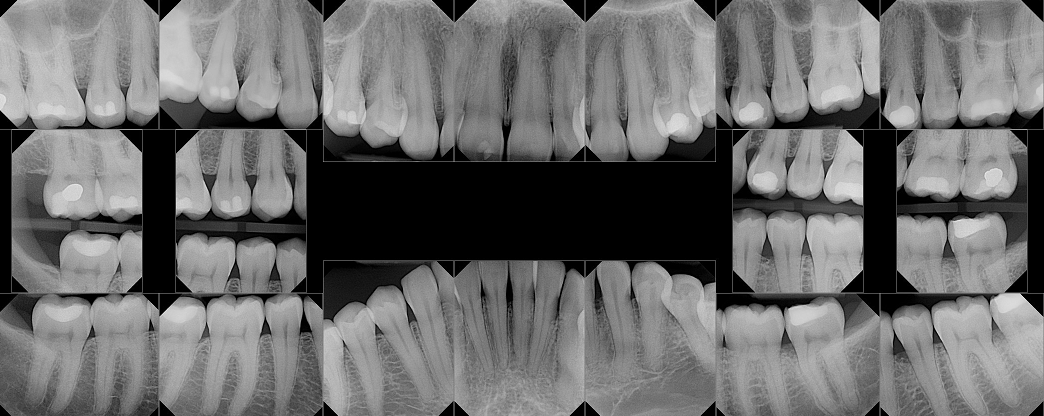

Example image of a full mouth xray

How many cavities do you see in the x-ray above? One? Five? Unless you're a dentist, you probably can't tell. In a hypothetical example, let's say Dr. Moe says you need three fillings, a root canal, and a crown. Dr. Larry says you need four fillings, and Dr. Curly says you need two fillings--when three different dentists give you three different diagnoses, who is right? Are one or more ripping you off? The resounding answer is possibly, but probably not.